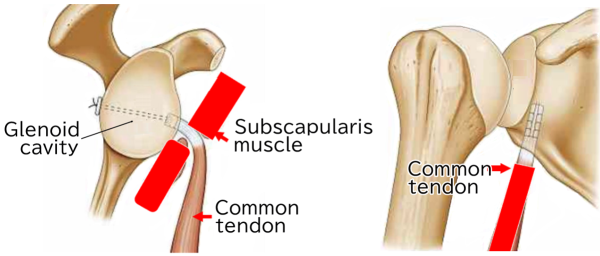

Coracoid process is a small hook-like structure which functions connected with multiple ligaments. The short head of biceps brachii and the coracobrachialis muscle attach to the coracoid process.

Joint tendons(Coracobrachialis muscle and the short head of biceps brachii)

I would like to introduce a new procedure called Coracoid tip-conjoined tendon complex transfer

★Joint tendons

Tie a medical cord around the joint tendons at 1 cm away from coracoid process.

Make a tunnel in the bottom part of the glenoid cavity of scapula.

Put the medical cord through the tunnel and tie it with metal buttons.

The edge of the coracoid process enters the scapula, and the joint ligaments will control the head of humerus. It can also repair the glenoid labrum.

This procedure can be described as a combination of Bankart repair and the ★joint ligaments procedure which will reinforce the strength of the joint, and control better a motion of the head of humerus.